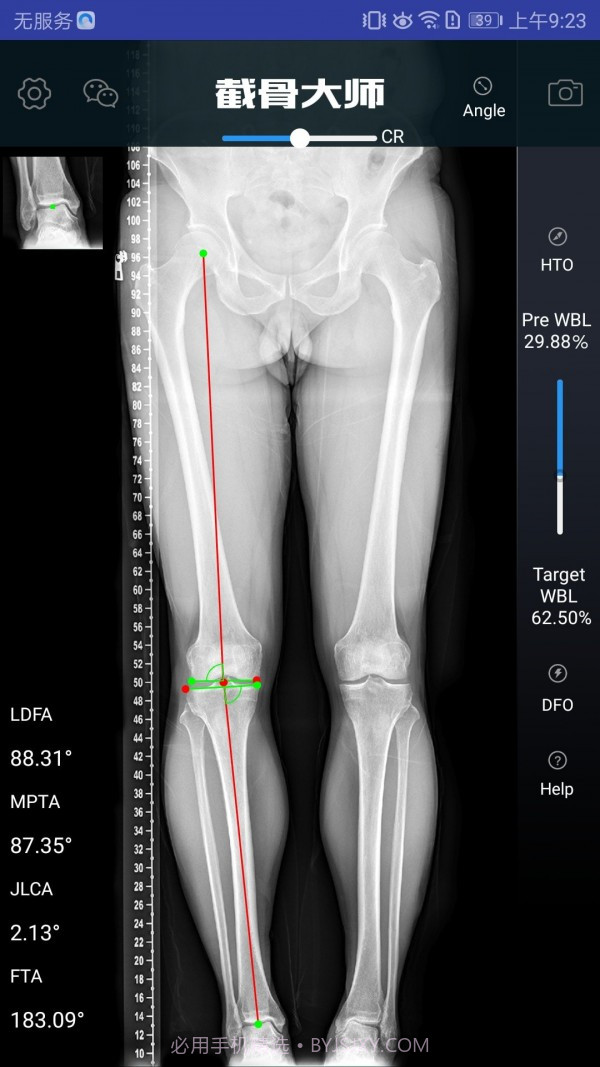

截骨大师真的是个宝藏APP,特别适合骨科医生和医疗人员使用。此外,它的手术模拟能力超级高效,能让医生在手术前清晰地了解手术效果,避免在实际操作中出现失误。而且,它的参数计算非常精准,真的是为医生的工作提供了很大的帮助。用这款软件,你不仅能节省大量准备时间,还能显著提高手术的成功率,对患者的治疗也有很大保障。作为医生,这款工具简直是必不可少的选择。

软件截图